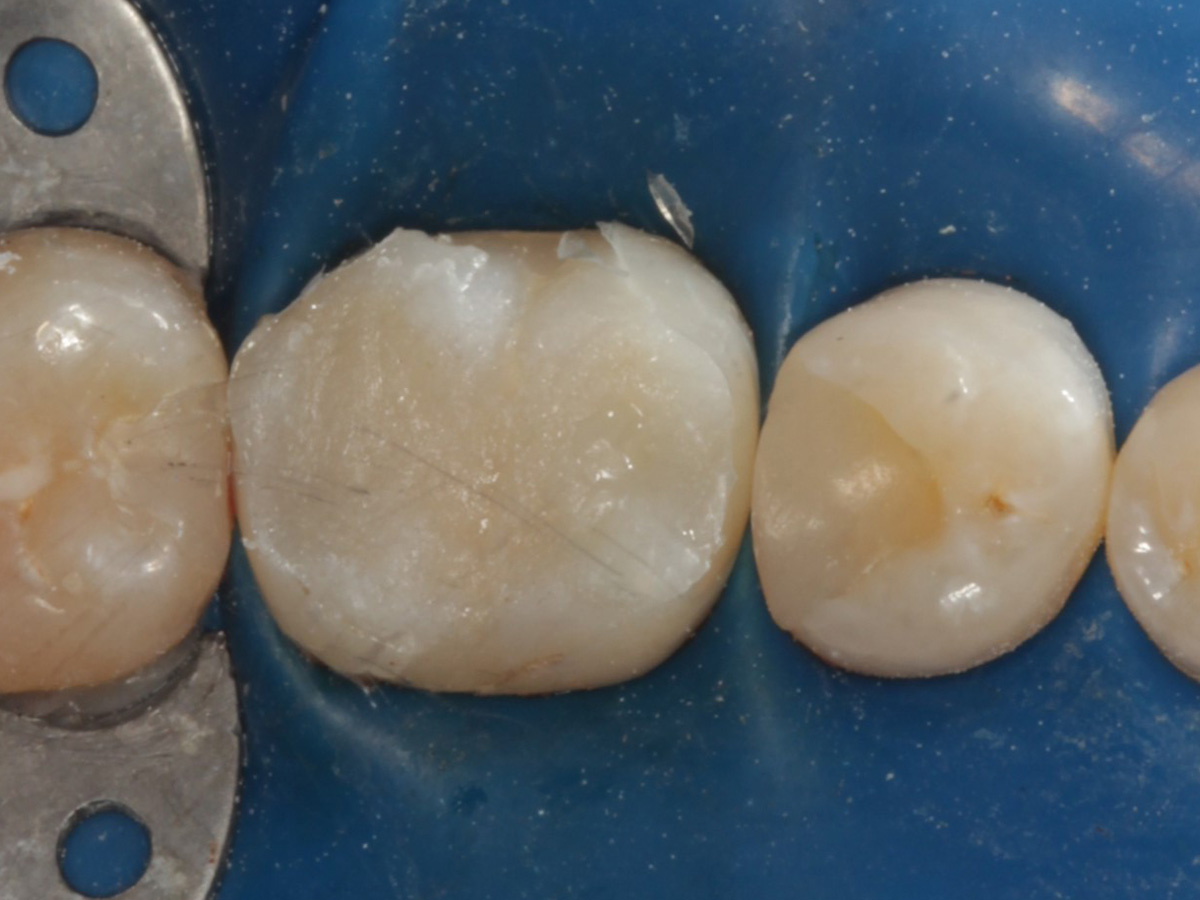

Kavitäten gefüllt (Injektion Moulding: Flowkomposit, erwärmtes Seitenzahnkomposit aus Karpule)

Abbildung 20

Abbildung 21

Zahnseidenkontrolle: kein Überschuss, satte Kontaktpunkte